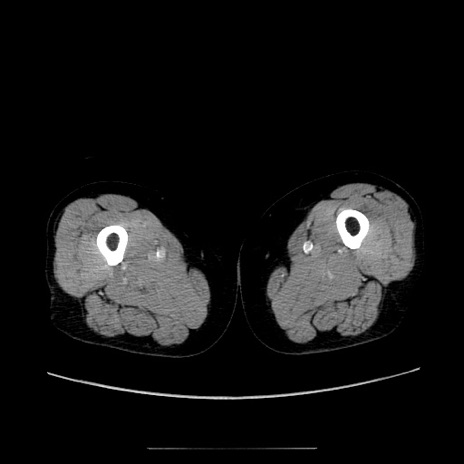

症例5(横断像)

【症例】70歳代女性

【主訴】お腹が張る

【現病歴】1週間くらい前から腹部膨満の自覚あり。昨日夜から増悪したため、本日救急外来受診。

【身体所見】意識清明、BT 36.5℃、BP 165/106mmHg、HR 80bpm、SpO2 98%、腹部:膨満、軟、自発痛・圧痛なし、触診にて不快感あり、腸蠕動音:減弱

【データ】WBC 12600、CRP 1.04